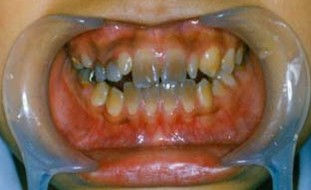

解析: 先天性无牙畸形 Total Anodontia

先天性无牙畸形的病因:外胚叶发育不全综合症、遗传性疾病。其临床表现:无汗、少汗、毛发稀疏、乳恒牙均可缺失、牙齿稀疏、牙形小、圆锥状。治疗:活动义齿修复。